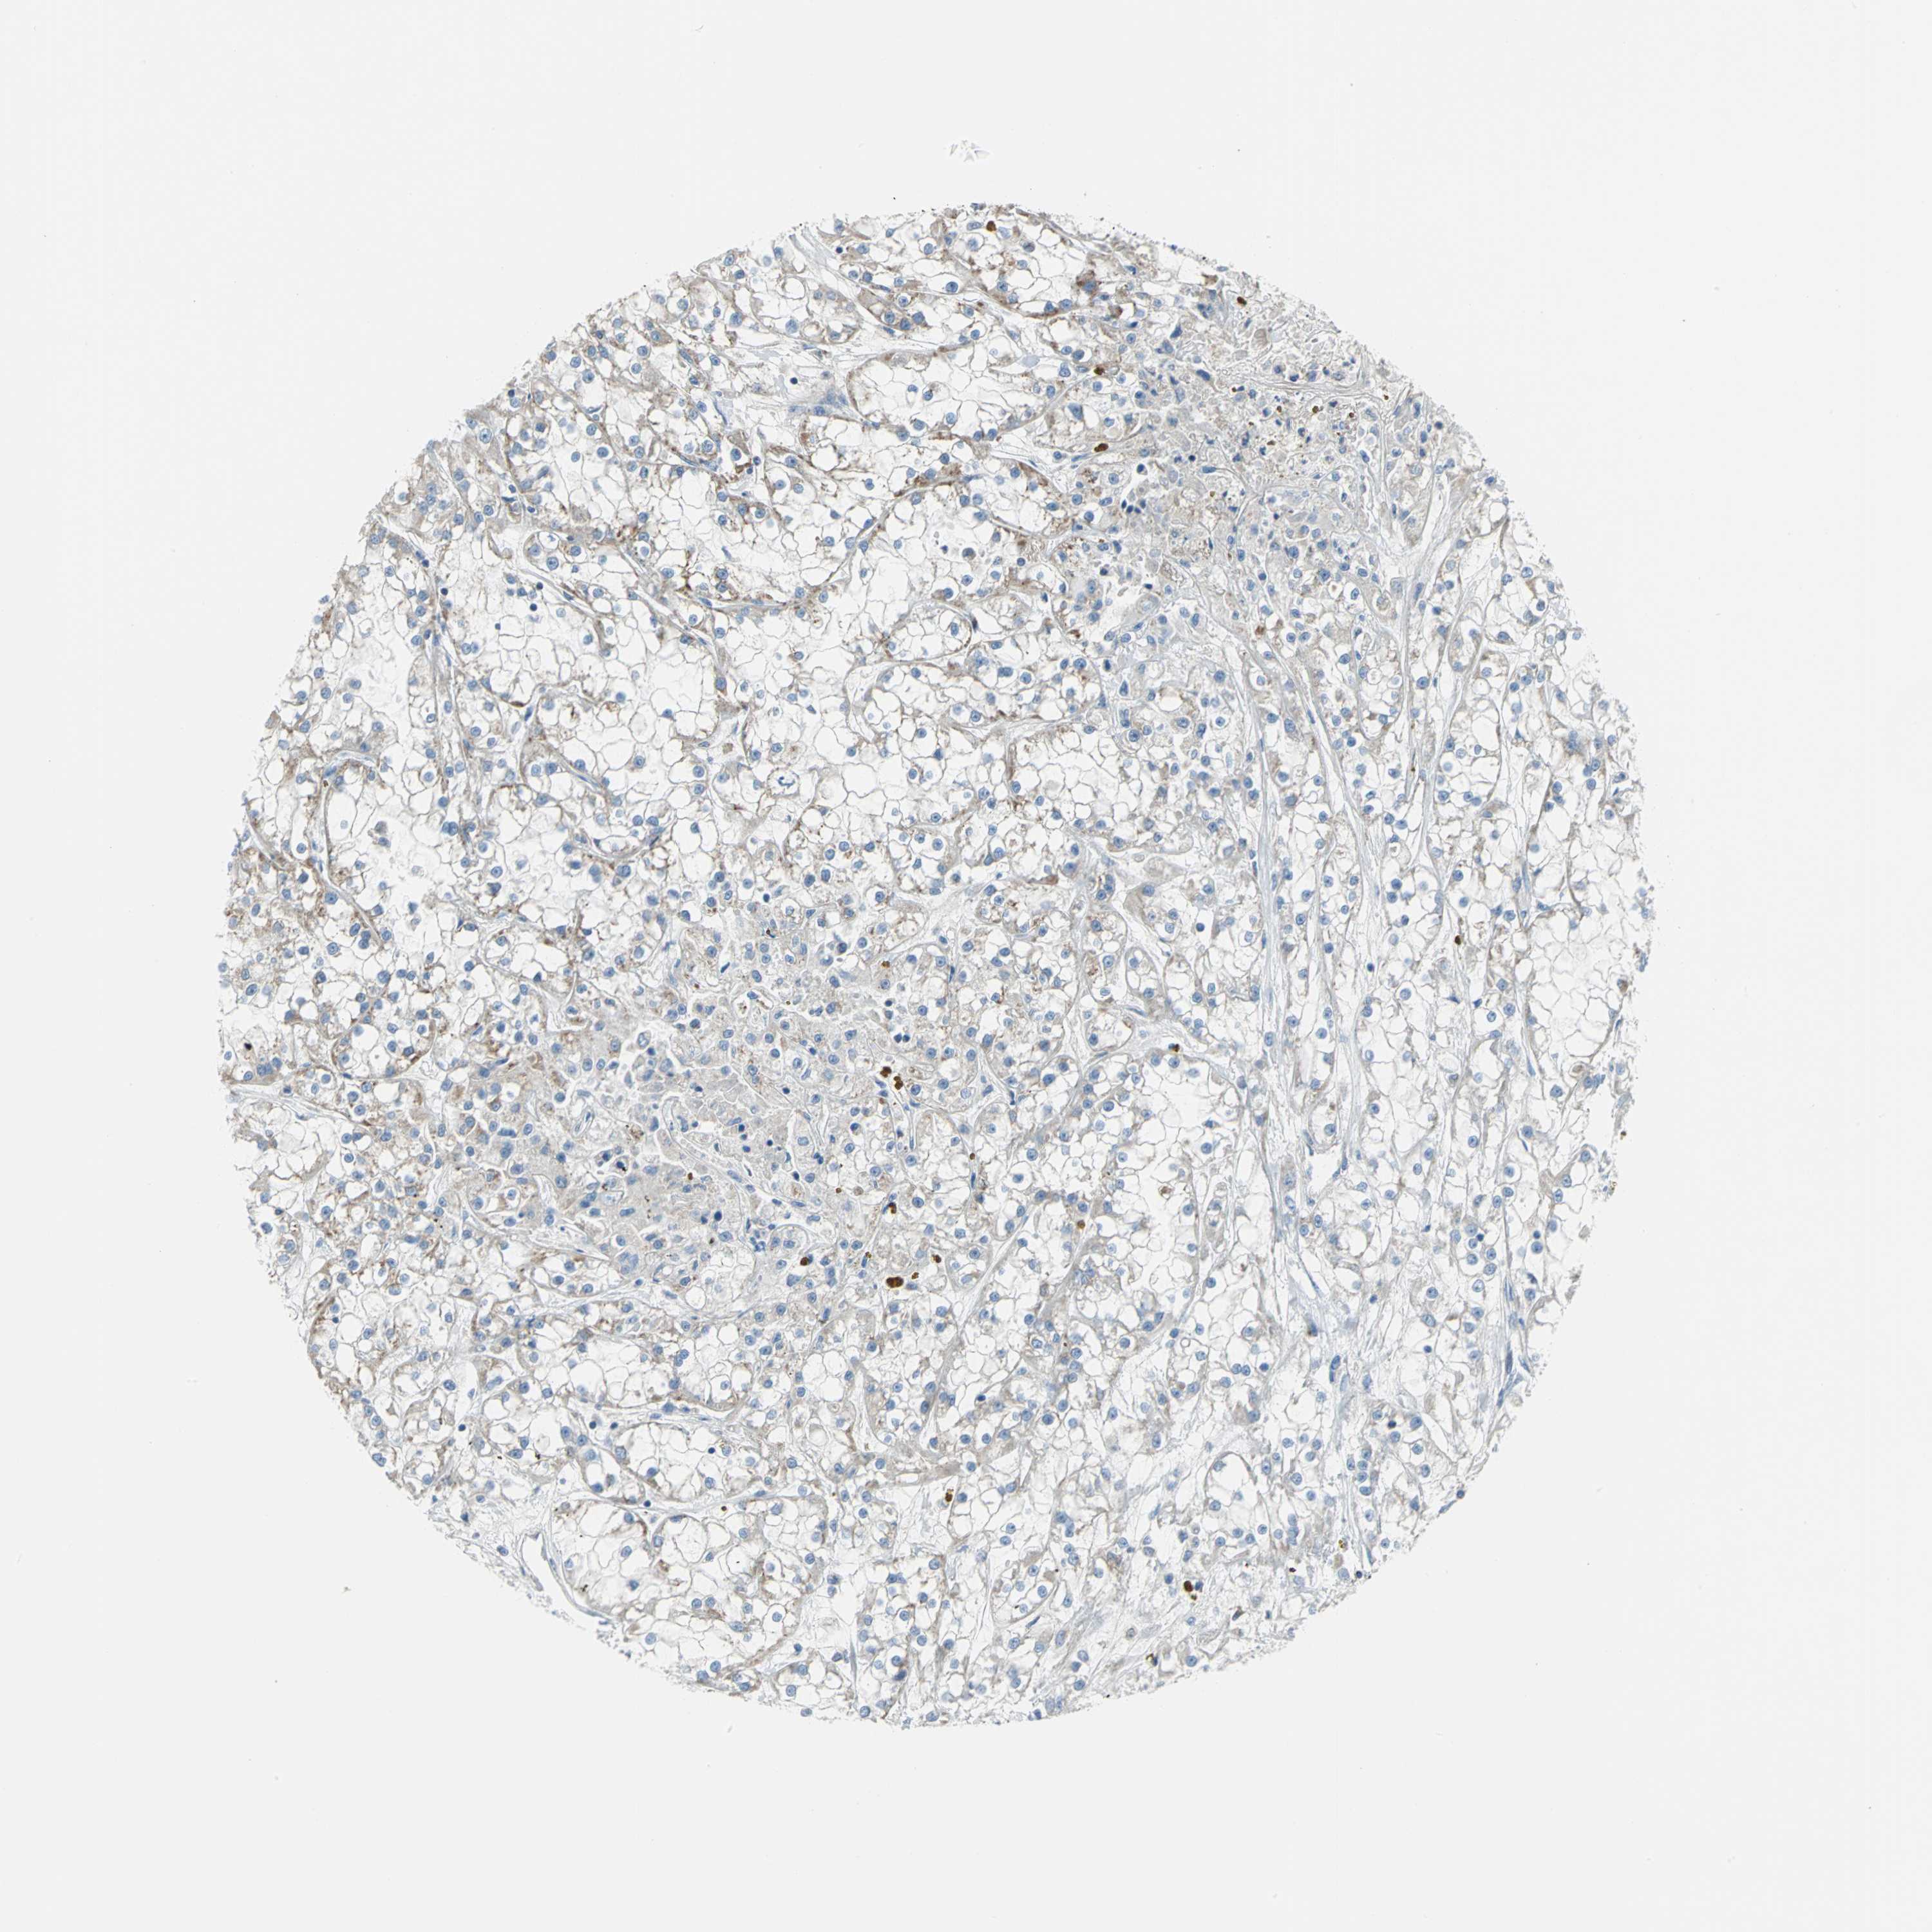

KIDNEY RENAL PAPILLARY CELL CARCINOMA (TCGA) - Interactive survival scatter ploti

The Survival Scatter plot shows the clinical status (i.e. dead or alive) for all individuals in the patient cohort, based on the same data that underlies the corresponding Kaplan-Meier plots. Patients that are alive at last time for follow-up are shown in blue and patients who have died during the study are shown in red.

The x-axis shows the expression levels (FPKM) of the investigated gene in the tumor tissue at the time of diagnosis. The y-axis shows the follow-up time after diagnosis (years). Both axes are complimented with kernel density curves demonstrating the data density over the axes. The top density plot shows the expression levels (FPKM) distribution among dead (red) and alive patients (blue). The right density plot shows the data density of the survived years of dead patients with high and low expression levels respectively, stratified using the cutoff indicated by the vertical dashed line through the Survival Scatter plot. This cutoff is automatically defined based on the FPKM cutoff that minimizes the p-score. The cutoff can be changed by dragging the vertical line or by entering a cutoff value in the square labeled "Current cut-off".

Under the Survival Scatter plot the p-score landscape (black curve; left axis) is shown together with dead median separation (red curve; right axis). Dead median separation is the difference in median mRNA expression between patients who have died with high and low expression, respectively. It is calculated as follows: median FPKM expression of dead patients with high expression - median FPKM expression of dead patients with low expression. This is intended to aid the user in visually exploring custom cutoffs and the associated p-scores and dead median separation.

Individual patient data is displayed and can be filtered by clicking on one or more of the category buttons on the top of the page. Categories describing expression level and patient information include: high, low, alive, dead, female, male and tumor stages. The scale of the x-axis can be toggled between linear and log-scale by clicking on the "x log" button. Mouse-over function shows TCGA ID, patient information and mRNA expression (FPKM) for each patient.

& Survival analysisi

Kaplan-Meier plots summarize results from analysis of correlation between mRNA expression level and patient survival. Patients were divided based on level of expression into one of the two groups "low" (under cut off) or "high" (over cut off). X-axis shows time for survival (years) and y-axis shows the probability of survival, where 1.0 corresponds to 100 percent.

ALOX15 is not prognostic in Kidney Renal Papillary Cell Carcinoma (TCGA)

TCGA RNA samplesi

RNA-seq data is reported as average FPKM (number Fragments Per Kilobase of exon per Million reads), generated by the The Cancer Genome Atlas (TCGA) .

Normal distribution across the dataset is visualized with box plots, shown as median and 25th and 75th percentiles. Points are displayed as outliers if they are above or below 1.5 times the interquartile range. FPKM values of the individual samples are presented next to the box plot.

Average pTPM 0.0

Number of samples 282